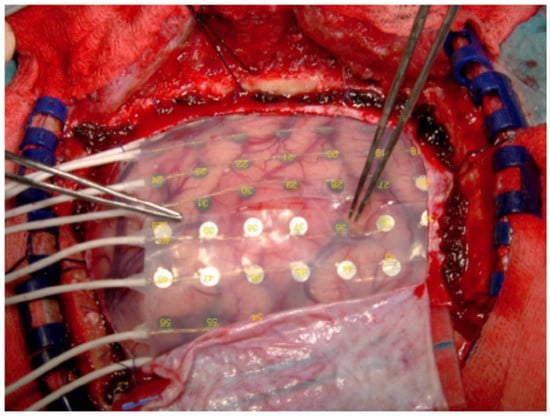

2.2. Invasive Brain-Computer Interfaces

- Miller, K.J.; Hermes, D.; Staff, N.P. The current state of electrocorticography-based brain–computer interfaces. Neurosurg. Focus 2020, 49, E2. [Google Scholar] [CrossRef]

- Leuthardt, E.C.; Miller, K.J.; Schalk, G.; Rao, R.P.; Ojemann, J.G. Electrocorticography-based brain computer interface-the Seattle experience. IEEE Trans. Neural Syst. Rehabil. Eng. 2006, 14, 194–198. [Google Scholar] [CrossRef] [PubMed]

- Dubey, A.; Ray, S. Cortical Electrocorticogram (ECoG) is a local signal. J. Neurosci. 2019, 39, 4299–4311. [Google Scholar] [CrossRef] [PubMed]

- Wang, P.T.; King, C.E.; McCrimmon, C.M.; Lin, J.J.; Sazgar, M.; Hsu, F.P.; Shaw, S.J.; Millet, D.E.; Chui, L.A.; Liu, C.Y.; et al. Comparison of decoding resolution of standard and high-density electrocorticogram electrodes. J. Neural Eng. 2016, 13, 026016. [Google Scholar] [CrossRef] [PubMed]

- Wittevrongel, B.; Khachatryan, E.; Carrette, E.; Boon, P.; Meurs, A.; Van Roost, D.; Van Hulle, M.M. High-gamma oscillations precede visual steady-state responses: A human electrocorticography study. Hum. Brain Mapp. 2020, 41, 5341–5355. [Google Scholar] [CrossRef]